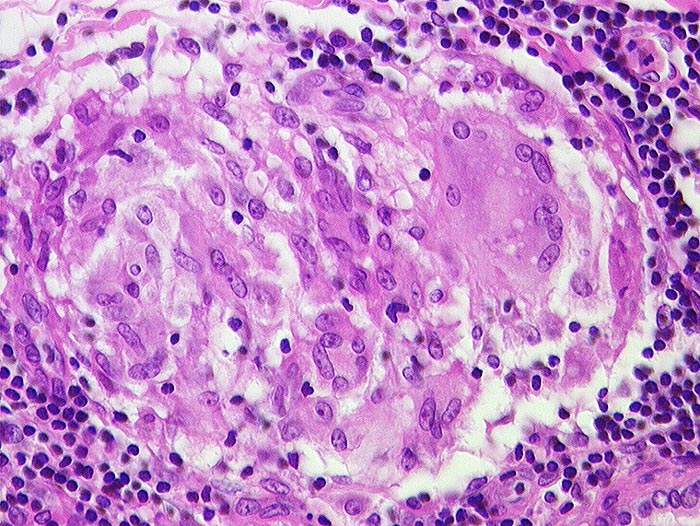

PathoPic ID 706 - Sarkoidosegranulom

Sarkoidosegranulom

Entzündung / Reparatur

Lymphknoten, Lunge

Lymphatische Gewebe, KM, Milz

Granulom aus Epitheloidzellen und einer Riesenzelle ohne Nekrosen.

Granulome in Lungen, Bronchialschleimhaut, Leber, Milz und Lymphknoten pulmonal

Histologie